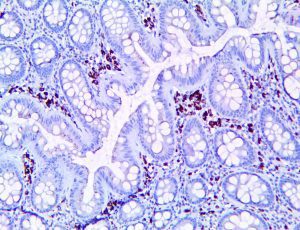

This activation induces inflammatory monocytes to highly express IL-6, starting a localized and then systemic cascade effect that results in hyperproduction of IL-6, which accelerates the inflammatory process. Because IL-6 also increases vascular permeability, excessive levels cause blood vessels to become very leaky. This, along with clotting factors released from vascular endothelial cells, stimulates the coagulation cascade, resulting in microthrombosis (tiny clots), which leads to ischemia and tissue death of the kidney, intestines, heart, liver, brain and extremities.